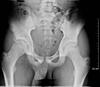

what is this finding called? association?

A

Segund fx

bony aculsion of anterolateral ligament

pathognominic for acl tear

associated with acl tear 75-100 percent of the time.